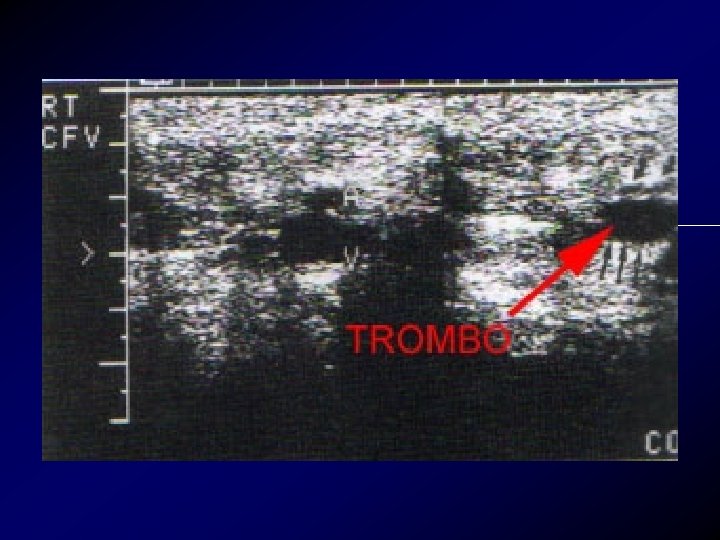

Diagnosi: Esami ecografici • L’ecografia o meglio l'eco color Doppler venoso, deve essere subito disponibile per non rallentare il processo di conferma diagnostica, può documentare una TVP dell'asse femoro-iliaco, sensibilità 93%, specificità 98%.